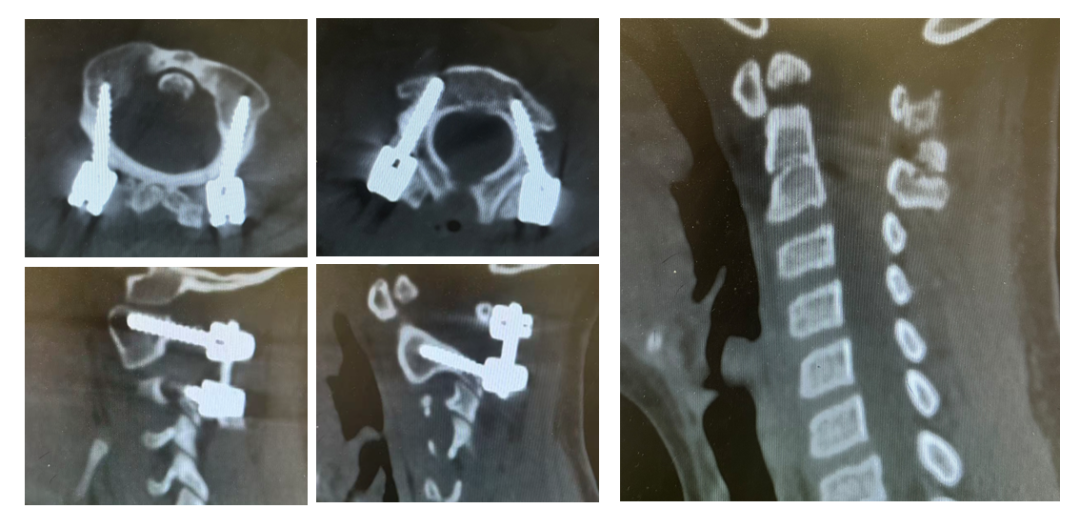

手术日,在麻醉与神经电生理监测团队的全程护航下,主刀医生许正伟主任首先巧妙利用颅骨牵引,为完全脱位的关节实现了初步松解与部分复位。随后,在高端术中导航系统( S 8 )的实时引导下,将椎弓根螺钉精准、安全地置入寰椎与枢椎的微小椎弓根内。利用螺钉提供的稳固杠杆,脱位的关节被轻柔而坚定地「推」回了正常解剖位置,实现了完美复位。最后,取自患儿自身的髂骨块被植入后方,为永久性骨融合打下基础。

术后影像显示:脱位完全矫正,内固定位置精确无误(图四)。次日,在康复师指导下,康康便戴着支具成功坐起。母亲眼中的担忧化为惊喜的泪光。术后第三天,引流管顺利拔除,伤口愈合良好。康康不再拿手抱着颈部,开始戴着支具下地(图五)。